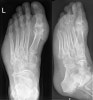

많은 경우 뼛속까지 침범하지 않지만 간혹 그런 경우도 있으므로, 수년에 한 번 정도는 X-ray를 찍어 보는 것도 괜찮습니다.

X-ray : 발가락 통풍(Gout)